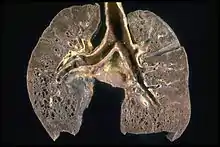

Respiratory tract

Localization to the lungs is by far the most common manifestation of sarcoidosis.[25] At least 90% of those affected experience lung involvement.[26] Overall, about 50% develop permanent pulmonary abnormalities, and 5 to 15% have progressive fibrosis of the lung parenchyma. Sarcoidosis of the lung is primarily an interstitial lung disease in which the inflammatory process involves the alveoli, small bronchi, and small blood vessels.[27] In acute and subacute cases, physical examination usually reveals dry crackles.[26] At least 5% of cases include pulmonary arterial hypertension.[26][28] The upper respiratory tract (including the larynx, pharynx, and sinuses) may be affected, which occurs in between 5 and 10% of cases.[29]

The four stages of pulmonary involvement are based on radiological stage of the disease, which is helpful in prognosis:[30]

- Stage I: bilateral hilar lymphadenopathy (BHL) alone

- Stage II: BHL with pulmonary infiltrates

- Stage III: pulmonary infiltrates without BHL

- Stage IV: fibrosis